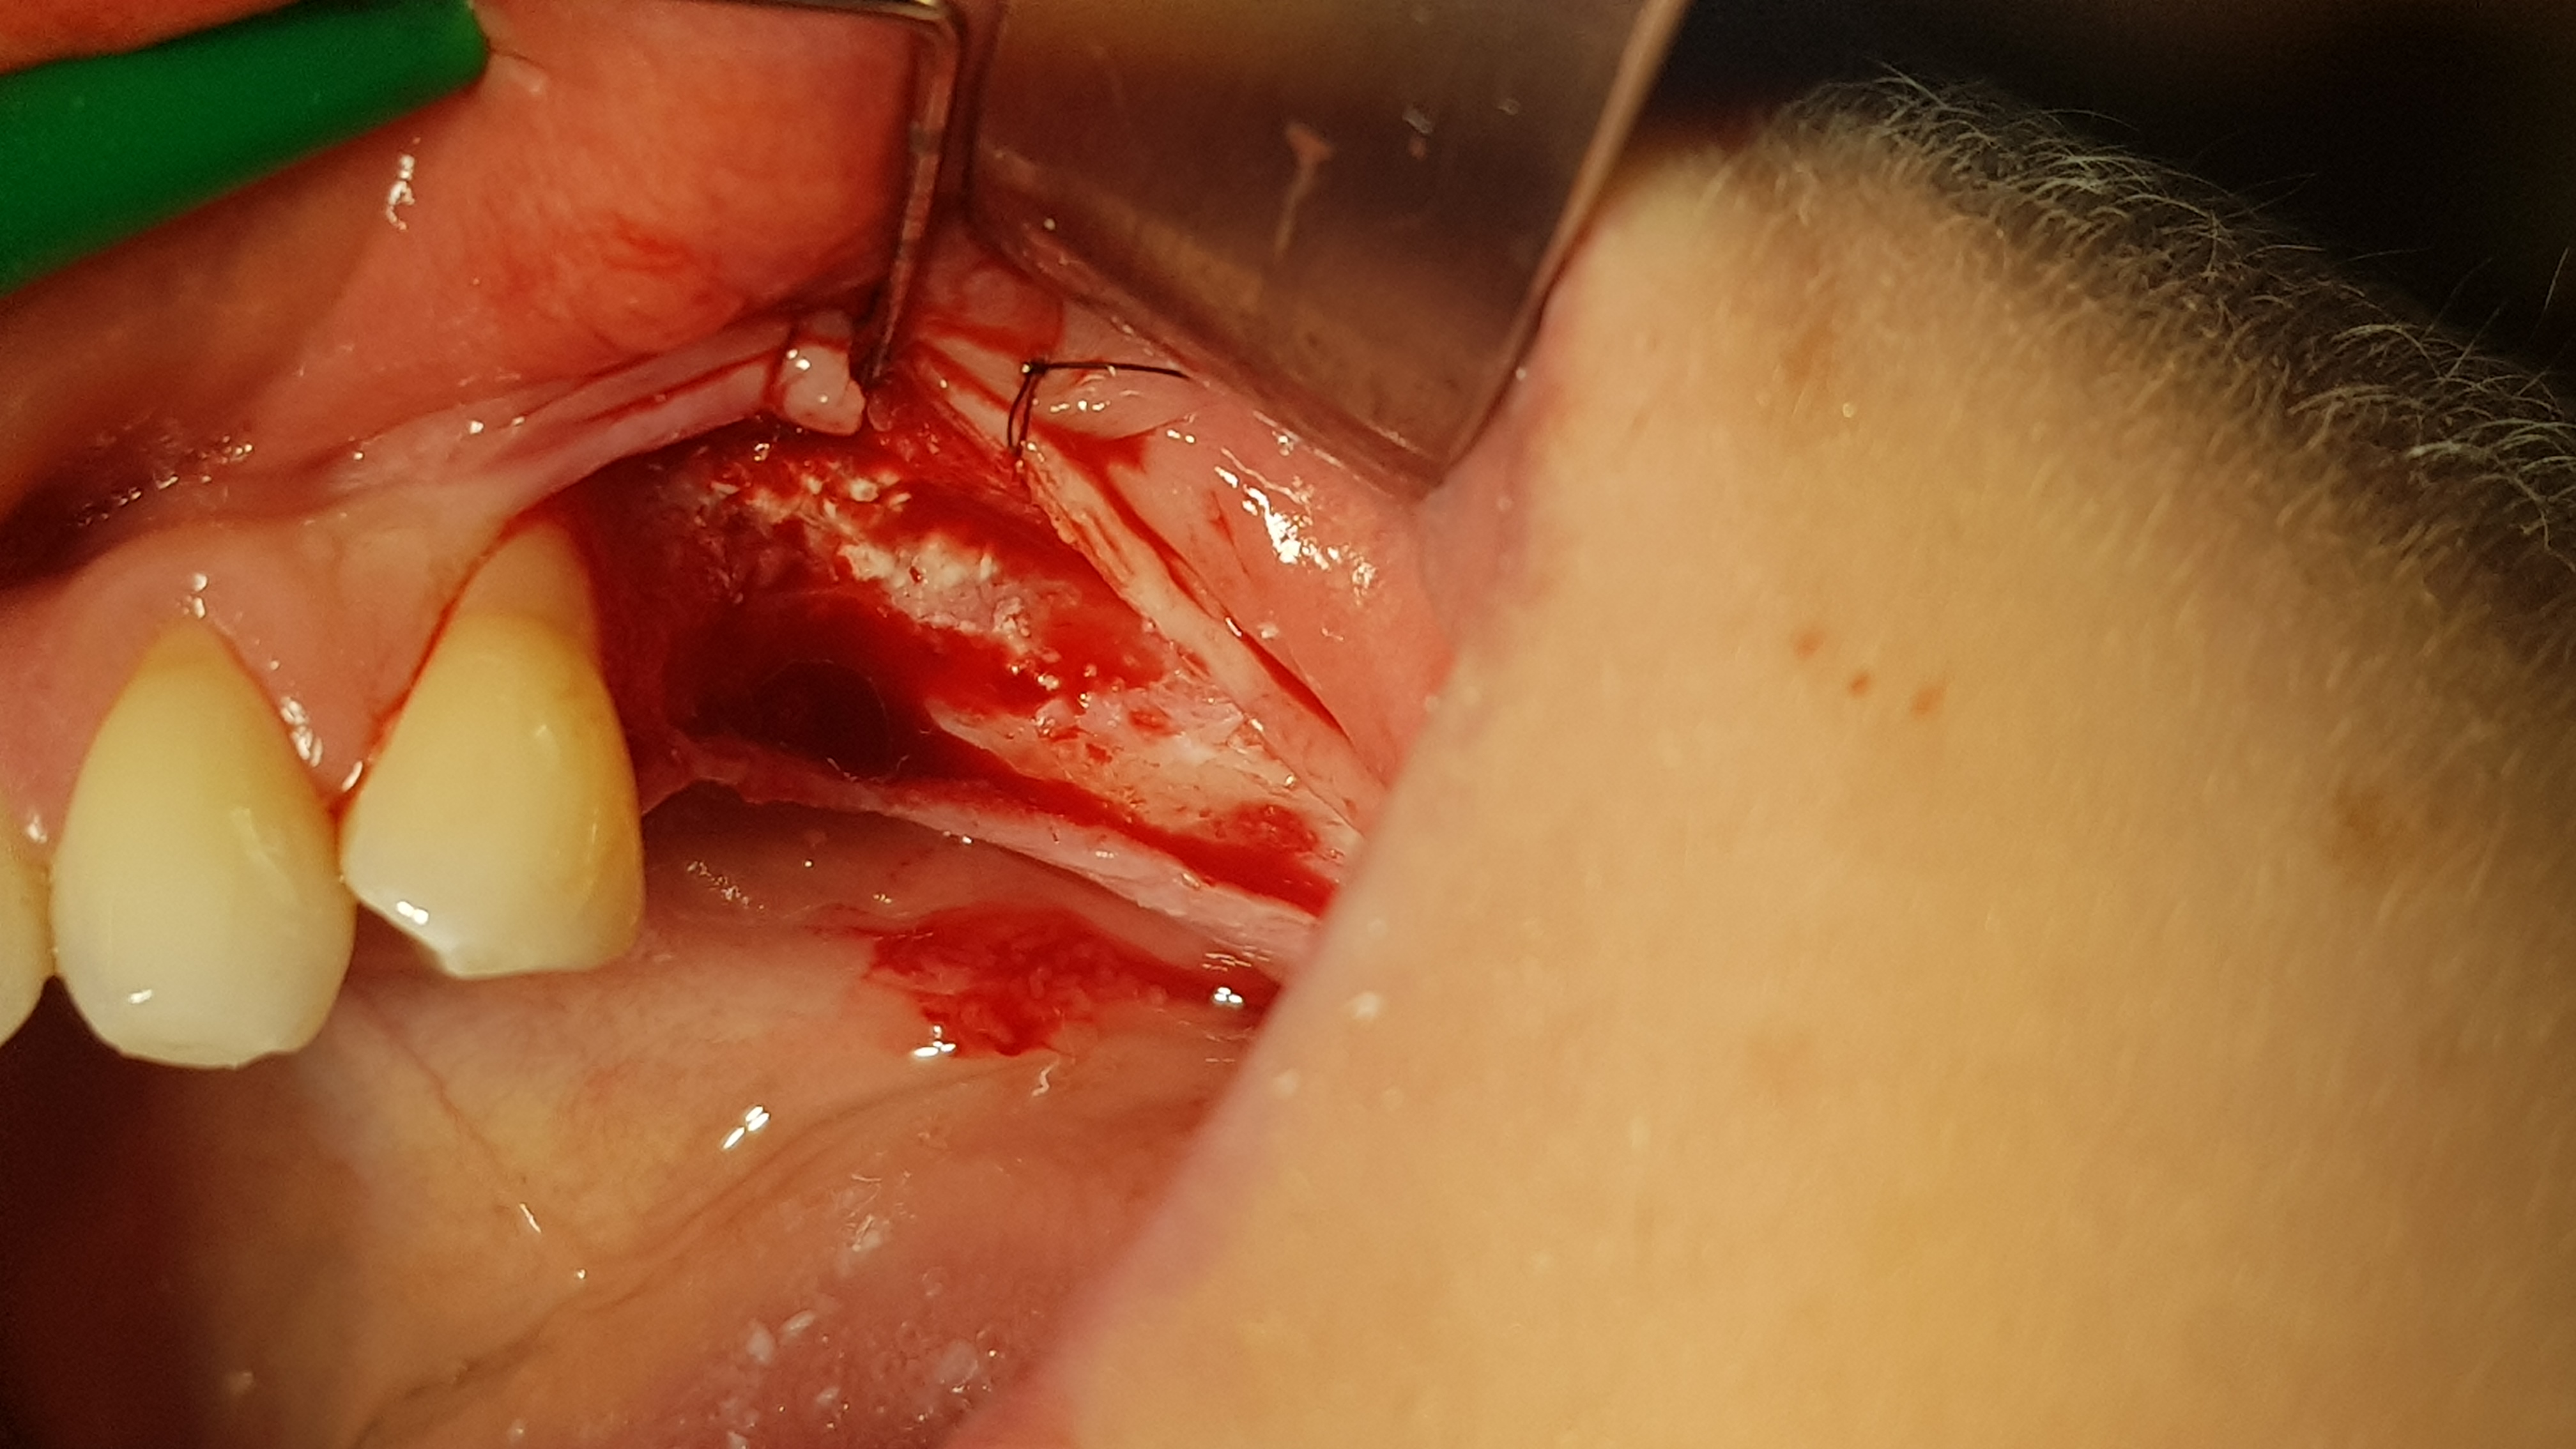

Brzegi rany zbliżono na odległość około 5 mm i zaopatrzono szwami (polidioksanon 4-0, igła okrągła kłująca, długość 16 mm, profil ½ koła). Po okresie 14 dni uzyskano ziarninowanie tkanki miękkiej. Drugi etap wykonano po 3 miesiącach. Dostęp do wyrostka wykonano w sposób typowy, jednym cięciem poziomym rozpoczynając na jego szczycie od okolicy 47, przedłużając do okolicy zęba 44 a następnie do przodu przez dziąsło zbite 44 i kończąc cięciem pionowym w połowie szerokości korony 44. Po odpreparowaniu tkanek miękkich uwidoczniono kość części zębodołowej, której powierzchnię poddano usunięciu pozostałości tkanek miękkich przy użyciu dedykowanych przez producenta wierteł z nasypem diamentowym.

Ryc. 6. Wytworzenie płata kątowego. Ryc. 7. Dekortykacja blaszki korowej.

Następnie wykonano otwory trepanacyjne w blaszce korowej kości o średnicy około 3 mm dochodząc do kości gąbczastej (ryc. 7). Taka średnica jest zalecana przez producenta dla lepszej retencji i utrzymania kształtu cementu regeneracyjnego w takim ubytku. Następnie po aktywacji umieszczono i uformowano cement na przygotowanej powierzchni kości (2 cm3) (ryc. 8).

Ryc 8. Uformowanie cementu na powierzchni wyrostka.   Ryc 9. Zaopatrzenie rany.

Kształt opracowano ręcznie przy użyciu raspatora i sterylnych gazików 5/5 cm. Następnie ranę przykryto płatem bez podcinania okostnej, a jedynie rozciągając go o kilka milimetrów dzięki wykorzystaniu pewnej elastyczności błony śluzowej. Ranę zaopatrzono szwami (polidioksanon 4-0, igła okrągła kłująca, długość 16 mm, profil ½ koła oraz nylon 5-0, igła odwrotnie tnąca, długość 12 mm, profil 3/8 koła) (ryc. 9). Pacjentka po zabiegu stosowała standardową antybiotykoterapię doustną (Amoksycylina 1.0 g co 12h 7 dni) oraz miejscowo płukanie jamy ustnej roztworem chlorcheksydyny. Rana goiła się prawidłowo, szwy usunięto w 10 dobie po zabiegu oraz wykonano kontrolne projekcje rtg, które wykazały prawidłowe utrzymanie cementu na wyrostku (ryc. 6-12).